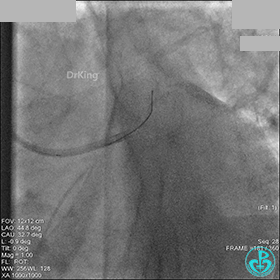

冠脉造影

入院次日冠脉造影显示粗大左主干末端中度狭窄,前降支开口严重狭窄,回旋支与前降支角度大,弥漫性长病变,严重狭窄,粗大右冠脉近中段弥漫性中重度狭窄。由于病变复杂,造影结束后先下台,择期再行介入治疗。

AL 1.0指引导管到位,简单短时尝试导丝不能顺利通过前降支或回旋支病变。改变策略处理右冠脉病变,计划植入2枚支架。AL指引导管到位,Sion blue导丝到达右冠脉远端。导丝通过后1.5mm及2.5mm球囊14~16atm充分扩张中段病变。